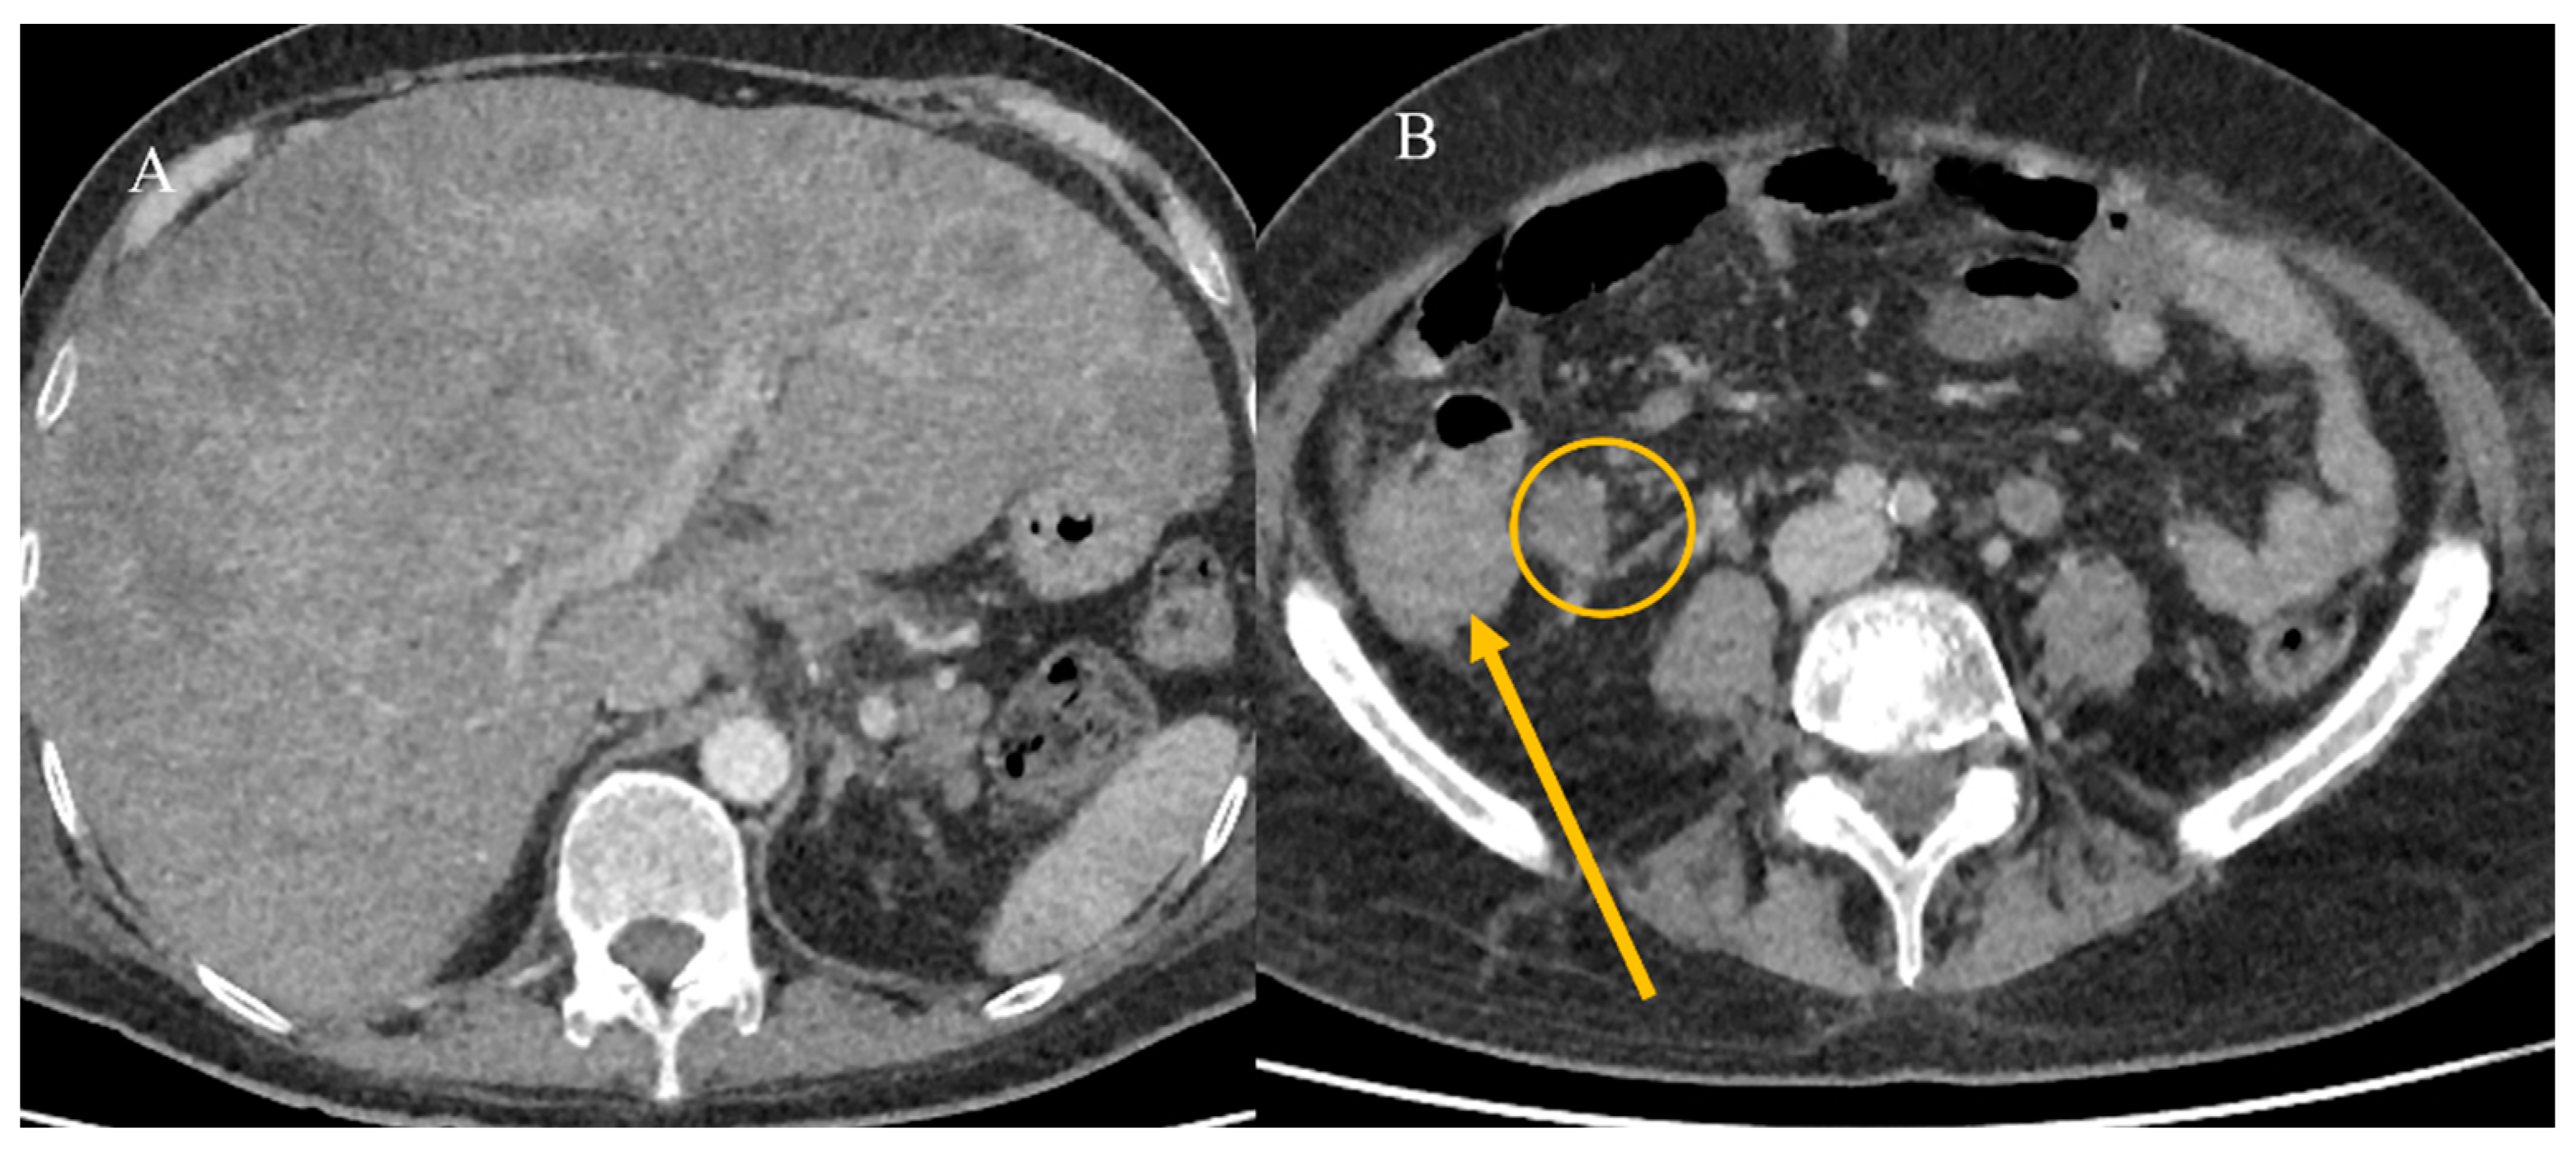

- Tuca, A.; Guell, E.; Martinez-Losada, E.; Codorniu, N. Malignant bowel obstruction in advanced cancer patients: Epidemiology, management, and factors influencing spontaneous resolution. Cancer Manag. Res. 2012, 4, 159–169. [Google Scholar] [CrossRef]

- Alshamsan, B.; Aseafan, M.; Badran, A.; Shaheen, A.; Elshenawy, M.A.; Bazarbashi, S.; Aljubran, A.H. Characteristics and outcomes of small bowel adenocarcinoma: 14 years of experience at a single tertiary hospital in Saudi Arabia. Mol. Clin. Oncol. 2023, 18, 17. [Google Scholar] [CrossRef]

- Kroepfl, V.; Bellotti, R.; Gasser, E.; Esswein, K.; Esser, H.; Kafka-Ritsch, R.; Öfner, D.; Perathoner, A. Small bowel neuroendocrine tumors: An analysis of clinical presentation, diagnostic workup and surgical approach—A single center retrospective study. Front. Surg. 2023, 10, 1072435. [Google Scholar] [CrossRef]

- Basendowah, M.H.; Ashour, M.A.; Hassan, A.Y.; Alshaynawi, S.; Alyazidi, L.K. Multiple small intestinal neuroendocrine tumors with findings of intestinal obstruction. Cureus 2021, 13, e17629. [Google Scholar] [CrossRef] [PubMed]

- Behi, H.; Omry, A.; Dallagi, R.; Changuel, A.; Troudi, D.; Khalifa, M.B. Diagnosing and managing small bowel neuroendocrine tumors presenting as acute obstruction in an elderly patient: A case report and comprehensive management overview. Int. J. Surg. Case Rep. 2024, 122, 110126. [Google Scholar] [CrossRef]